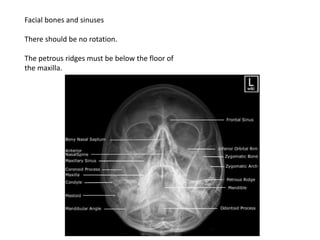

Facial bones and sinuses

There should be no rotation.

The petrous ridges must be below the floor of

the maxilla.